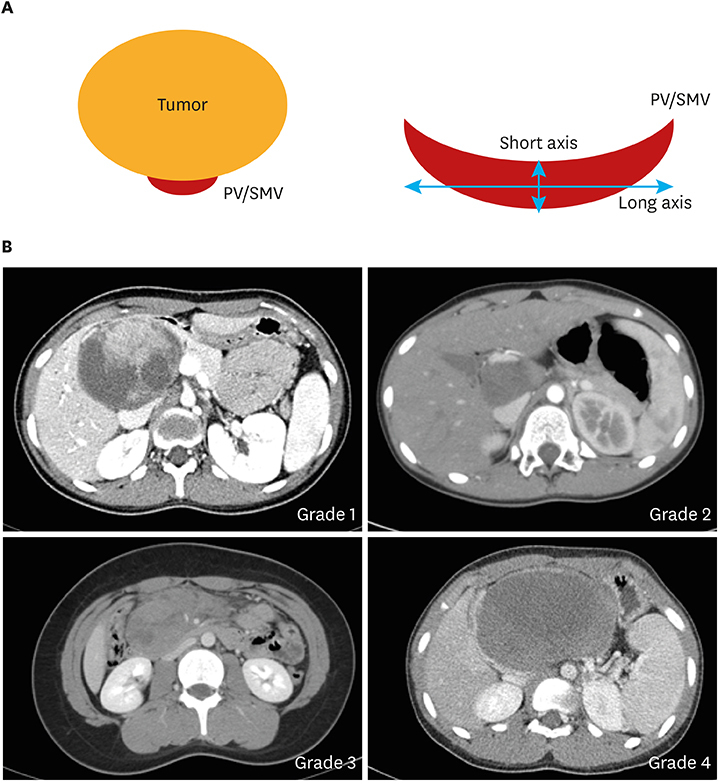

To evaluate the difficulty of MIS in each patient, we investigated tumor size and mass size/abdominal diameter (MS/AD) ratio. The degree of vascular abutment in the portal vein (PV), superior mesenteric vein (SMV), and splenic vein (SV) was also calculated. These parameters were measured using the preexisting abdominal CT. Since the size of the abdominal cavity in children varied by age and physical condition, the tumor size alone does not directly reflect the degree of operative difficulty. We measured the width of the abdominal cavity (abdominal diameter [AD]) at the level of the largest point of each tumor and calculated relative figures for the standardization of tumor sizes by the size of the abdominal cavity. We also calibrated the degree of compression in each vessel around each tumor (Fig. 1).

Fig. 1

Degree of PV or SMV compression. (A) PV compression model and (B) Grades 1–4 in computed tomography imaging.

Grade 1, PV or SMV abutment; Grade 2, long-axis < short-axis ×2; Grade 3, long-axis > short-axis ×2; Grade 4, complete collapse; PV, portal vein; SMV, superior mesenteric vein.

A total of 28 patients had either PV or SMV abutment (Table 6). The number of PV or SMV abutment in the OP group was larger compared with the MIS group (p<0.001). Although the number of grades 1 and 2 PV and SMV compression between the two groups did not show statistical difference, grades 3 and 4 showed statistical difference (p<0.001). There were total of 34 SV compressions, none of which showed any difference.

Among many parameters, the most important factors are tumor size, MS/AD ratio, and the degree of abutment or compression on PV or SMV. In this study, tumor size, MS/AD ratio, and operative time were analyzed according to the surgery and approach, whether open or laparoscopic/robotic. The tumor size and MS/AD ratio was significantly different between open and minimally invasive enucleation and DP/SSDP. From these results, patients with larger tumor size or higher MS/AD ratio should undergo open surgery rather than MIS. In our experience, tumors with compression grade 3 or higher do not offer appropriate surgical field for the surgeon, making ligation of the perforation vessel extremely difficult. Since clipping was not applicable in most cases, open suture ligation was necessary. In this study, there were 4 cases of open conversion due to vessel encasement (n=2), bleeding (n=1), and pancreatic duct injury during enucleation (n=1).

There is a tendency in recent literature siding with MIS. Even in our center, we can notice that the MS/AD ratio in the MIS group is increasing (Fig. 3). With increasing evidence proving superiority of MIS over OP, surgeons are performing MIS despite bigger masses and harder cases. To reduce the risk of MIS, surgeons must carefully select patients feasible for MIS. We carefully suggest MS/AD ratio smaller than 0.3 and PV/SMV compression of grade 2 or lower, to be considered a feasible candidate for MIS. As mentioned before, SV compression is not an absolute indication. Since, SPT cases are rare, it is very difficult for a single pediatric surgeon to complete a learning curve. However, with the advancement in laparoscopic technique in other diseases, we believe that the range of surgical indications will expand.

Fig. 1 Degree of PV or SMV compression. (A) PV compression model and (B) Grades 1–4 in computed tomography imaging. Grade 1, PV or SMV abutment; Grade 2, long-axis < short-axis ×2; Grade 3, long-axis > short-axis ×2; Grade 4, complete collapse; PV, portal vein; SMV, superior mesenteric vein.